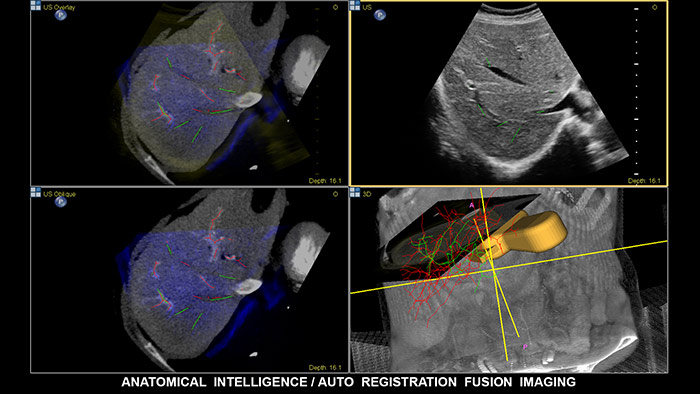

La fusión de imágenes combina las ventajas inherentes de la adquisición de imágenes de multimodalidad directamente en el sistema de ultrasonidos mediante seguimiento electromagnético. Al combinar TC/RM/PET con ultrasonidos en tiempo real y la posición en tiempo real del paciente, el profesional sanitario cuenta con una potente herramienta de diagnóstico y, al mismo tiempo, limita la radiación debido a que se necesitan menos exploraciones de confirmación; de este modo, se potencia la productividad del departamento. EPIQ, con su exclusivo sistema de ultrasonidos con inteligencia anatómica (AIUS), ofrece fusión de imágenes con registro automático de volúmenes de TC/RM y ultrasonidos, tarea para la que se emplea una décima parte del tiempo que suele durar la alineación. La navegación guiada por aguja es una herramienta que mejora el rendimiento en las intervenciones hepáticas más complejas; además, se ha demostrado que mejora el flujo de trabajo y reduce la exposición a la radiación al necesitarse menos exploraciones de confirmación. EPIQ de Philips incluye una gama completa de soluciones, entre las que cabe destacar las siguientes: CIVCO eTrax™, el localizador de aguja adaptativo de Philips y los localizadores de aguja coaxial de Philips. De esta manera, el profesional sanitario, al disponer de una compatibilidad tan amplia con los dispositivos de biopsia y ablación, es libre de elegir las mejores herramientas para el procedimiento en función del grado de complejidad.

Tome decisiones con seguridad incluso en casos diagnósticos complicados con ayuda de las funciones de fusión de imágenes y navegación guiada por imagen de Philips. El flujo de trabajo agilizado permite que los profesionales sanitarios consigan una fusión eficaz de TC/RM/PET con ultrasonidos en tiempo real; a su vez, la navegación guiada por aguja ayuda a guiar la biopsia de lesiones pequeñas y de difícil acceso.